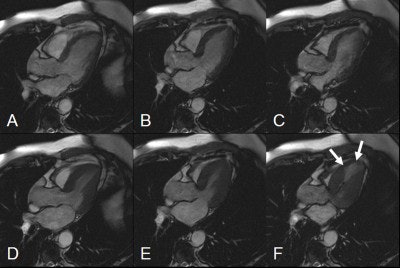

![]() |

| The same patient. Echocardiography in corresponding apical LVOT view. Top, diastolic (left) and systolic (right) image in rest study. Bottom, diastolic (left) and systolic (right) image during infusion of 10 µg/kg/min. of dobutamine (Stress). Arrows show akinesis in rest and under stress indicating scar corresponding to MRI. Asterisk shows slight improvement of basal segment under stress, indicating viable but ischemic myocardium as suggested on MRI. Images courtesy of Dr. Peter Hunold. |